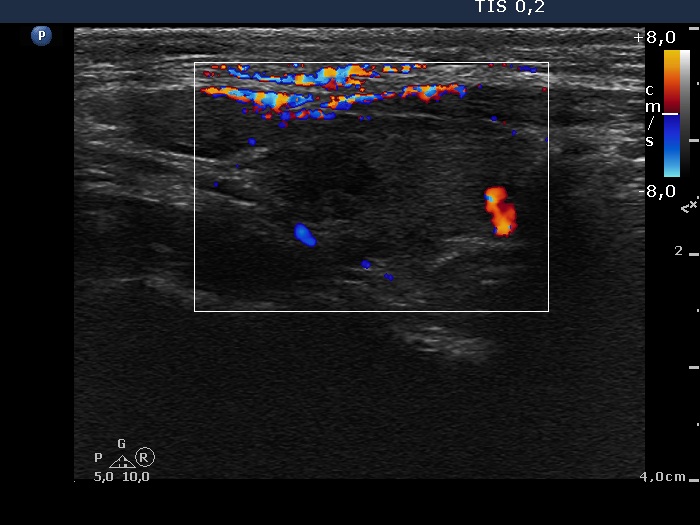

Left lobe, longitudinal scan, color Doppler mode. The vascularization is decreased.